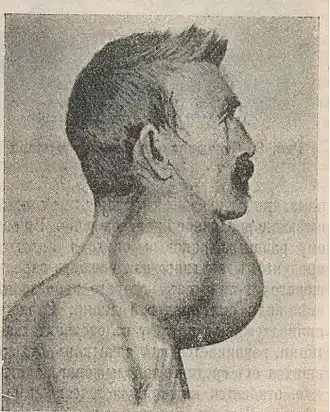

Рак щитовидной железы. Илл. 1914 года | |

- Рак щитовидной железы